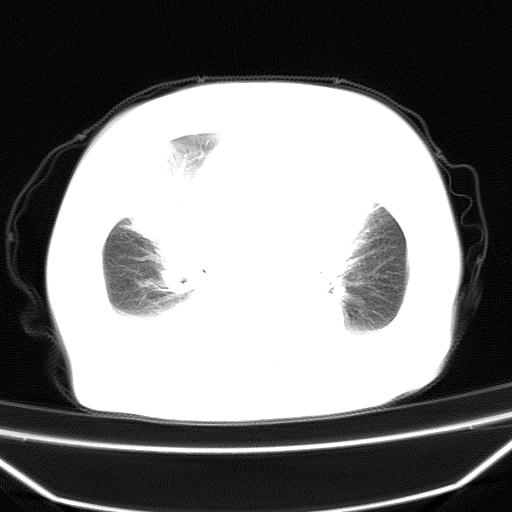

以下是引用jiangjing在2008-4-20 10:43:00的发言:[br]结合病史支持 冠心病[冠状动脉钙化],心功能不全,肺淤血、肺水肿,双侧胸腔与斜裂积液

以下是引用liuyue在2008-4-19 22:25:00的发言:[br]先考虑:1.心衰伴肺水肿、双侧胸腔积液、叶间积液、双下肺不完全性肺不张; [br] 2.冠状动脉粥样硬化。

以下是引用lijuanln在2008-4-19 23:05:00的发言:[br]两侧胸腔积液,肺水肿[br]心包积液[br]提示心衰